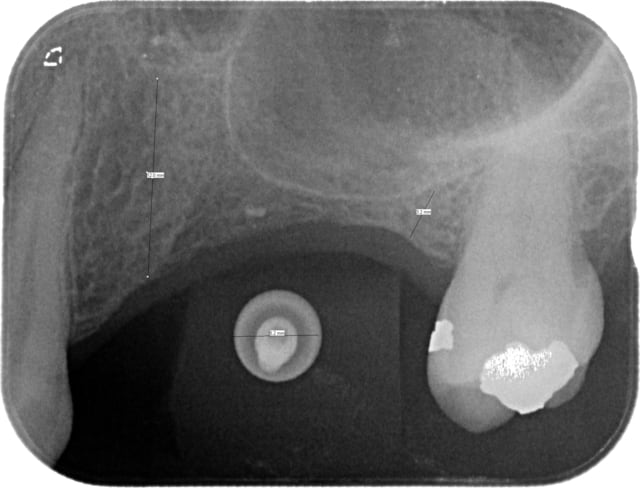

Je souhaitais proposer un bridge(24-25-26) sur implants 24 et 26.

J'ai fait une rétroalvéolaire de la zone: à priori pas de soucis pour 24, malheureusement j'ai environ 3mm d'os en 26.

L'implant en 26 doit être plus en mésial que ton trait de mesure, là où il y a le moins d'os...

bon, elle est belle ta rétroalvéolaire mais tu ne demandes pas une 3D (cone beam ou scan) avant de poser tes implants???